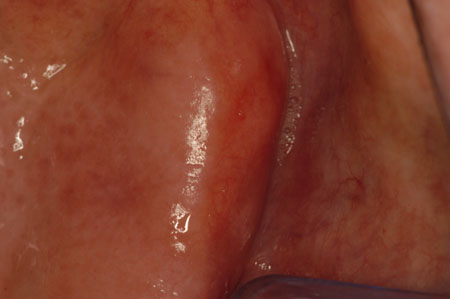

As lesões da mucosa oral potencialmente malignas (pré-cânceres orais) incluem, principalmente, algumas leucoplasias e eritroplasia (também conhecida como eritroleucoplasia). A eritroplasia, embora muito menos comum que as leucoplasias, tem maior potencial maligno. A eritroplasia apresenta-se como uma placa vermelha aveludada e, pelo menos, 85% dos casos mostram franca malignidade ou displasia epitelial grave.[66]Quah SR, Cockerham WC, eds. International encyclopedia of public health. 2nd ed. Oxford: Elsevier; 2017. A leucoplasia, especialmente quando apresenta lesões vermelhas misturadas (leucoplasia salpicada), é potencialmente maligna. Ao utilizar um sistema microscópico binário de classificação, em que as lesões são classificadas em displasia de baixo risco ou displasia de alto risco, esta última foi um indicativo significativo na avaliação da transformação maligna.[67]Liu W, Wang YF, Zhou HW, et al. Malignant transformation of oral leukoplakia: a retrospective cohort study of 218 Chinese patients. BMC Cancer. 2010 Dec 16;10:685.

[Figure caption and citation for the preceding image starts]: EritroplasiaCortesia do Dr. James Sciubba; usado com permissão [Citation ends].